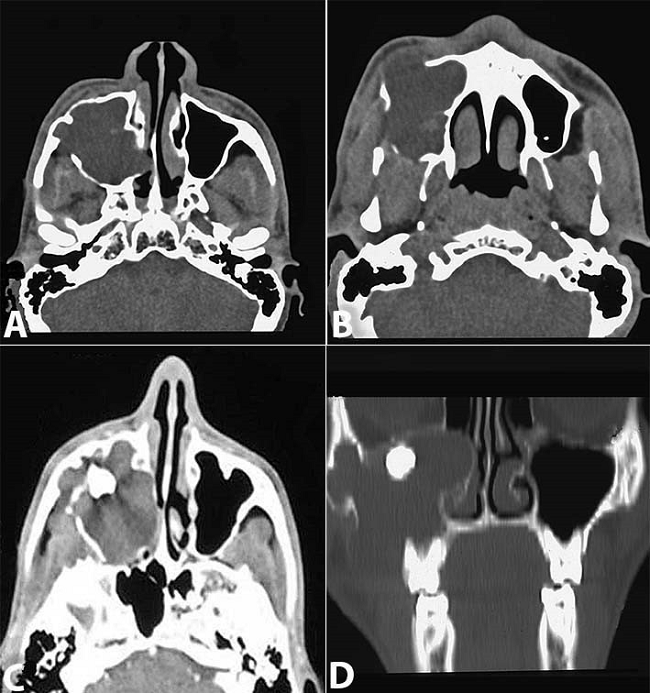

Routine laboratory parameters were normal. Radiological examination depicted a single unilocular radiolucency with smooth, corticated margins extending from the root apex of the right maxillary canine to the right maxillary tuberosity region. The radiolucency was associated with an impacted maxillary right third molar displacing it superiorly into the opacified right maxillary antrum. Destruction of the posterior wall of the sinus was also evident. The involved teeth showed no deviation; however, slightly resorbed roots were detected with right maxillary first and second premolars and right maxillary first molar. To visualize the lesion in more detail, computed tomography (CT) was performed, which revealed a large, well-defined, non-enhancing, hypodense osteolytic lesion (5.2 × 5 × 4.7 cm) with a well-defined margin. The lesion involved the right maxillary bone and the maxillary sinus, and caused complete opacification of the right antrum and displacement of the right maxillary third molar to the anteromedial wall of the sinus (Figure 2). The expansile cystic lesion caused thinning of the antral walls and erosion of the buccal cortical bone of the right maxillary bone. Based on these observations, a tentative pre-operative diagnosis of dentigerous cyst associated with the right maxillary third molar was proposed.